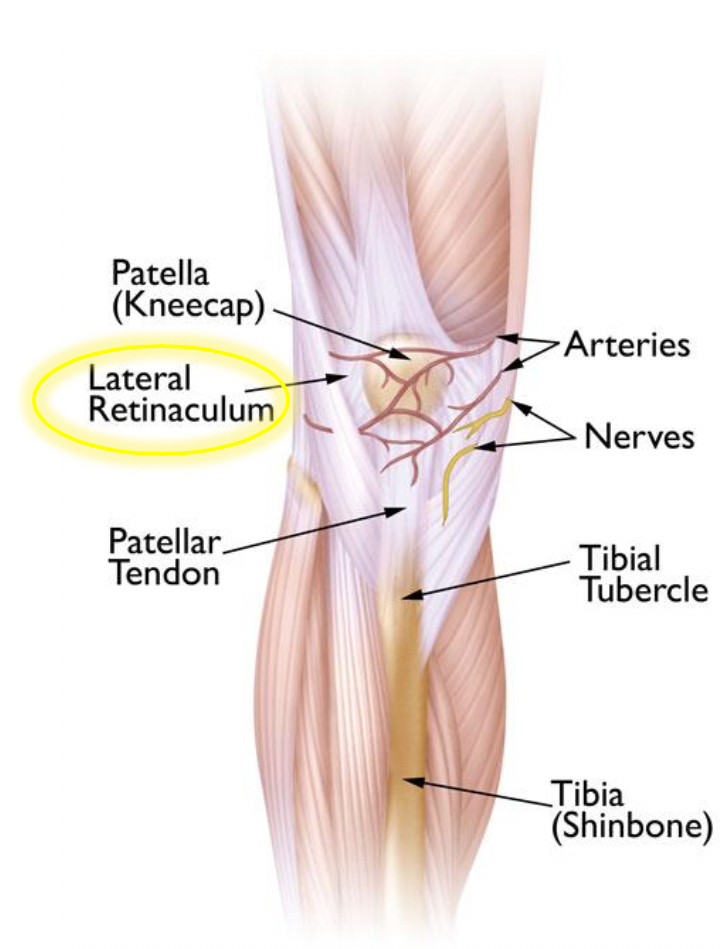

Patellar maltracking due to a functional malalignment or dynamic valgus may be an underlying cause for this clinical entity. Knee surgery, particularly repair to the anterior cruciate ligament using your own patellar tendon as a graft, increases the risk of the syndrome. The patellofemoral pain syndrome is a clinical entity which leads to anterior knee pain in patients without any pathological changes at the cartilage of the patellofemoral joint.

During arthroscopy, your surgeon inserts a small camera, called an arthroscope, into your knee joint. Crutch use, usually necessary for one to three weeks after surgery; Patellofemoral pain syndrome may be caused by overuse, injury, excess weight, a kneecap that is not properly aligned (patellar tracking disorder), or changes under the kneecap.

The patella, also called kneecap, is a small flat triangular bone located at the front of the knee joint. The main symptom of patellofemoral pain syndrome is knee pain, especially when you are sitting with bent knees, squatting, jumping, or using the stairs (especially going down. Treatment for patellofemoral pain syndrome.